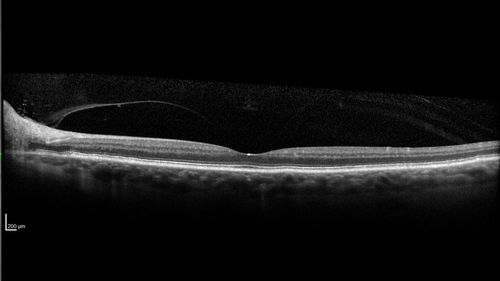

Stellate non-hereditary idiopathic foveomacular retinoschisis (SNIFR) and optic nerve drusen

84 year old man No visual complaints. Not diabetic, cataract surgery 8 years ago. Meds: Omeprazole, Tamsulosin (Flomax)

VA 20/32 OD, 20/20 OS